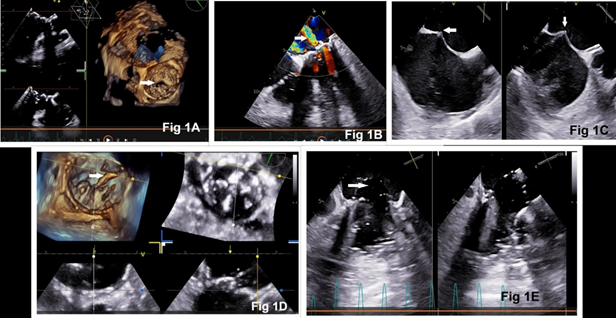

A 52-year-old female was admitted with complaints of worsening dyspnea (New York Heart Association class III-IV) and palpitations. She underwent closed mitral valvotomy in 1997 for rheumatic mitral stenosis, followed by mitral valve replacement and aortic valve replacement with bioprosthetic valves in 2012. Transthoracic echocardiography (TTE) revealed a thickened and fibrosed bioprosthetic heart valve (BHV) at the mitral position with restricted mitral valve opening, causing severe mitral stenosis (MS) and moderate mitral regurgitation (Fig. 1A, 1B). The transvalvular gradients across the mitral valve were 41/19 mmHg (peak/mean). The BHV at the aortic position was functioning normally with no significant gradient across the valve and mild aortic regurgitation. There was severe tricuspid regurgitation, and the estimated pulmonary artery systolic pressure was 80 mmHg. The left ventricular function was normal, while there was moderate right ventricular systolic dysfunction.

The estimated EuroSCORE II for a redo-valve surgery was high (10.01%). The ‘Heart-team’ suggested transcatheter mitral valve-in-valve replacement (TMViVR), and the patient’s informed consent was obtained. TMViVR was performed in a hybrid operating room under general anesthesia with all standard cardiac monitoring, including 3-D transesophageal echocardiography (TEE). A balloon-expandable 23 mm MyvalTM transcatheter mitral valve (Meril Life Sciences Pvt. Ltd., Vapi, Gujarat, India) was deployed by trans-septal puncture through the femoral route uneventfully (Fig. 1C, 1D, 1E). Anticoagulation therapy was commenced with intravenous unfractionated heparin followed by oral warfarin. On the third day of the procedure, the patient developed acute heart failure with severe breathlessness requiring intubation and mechanical ventilation. Soon, the patient developed cardiogenic shock requiring high-dose inotropes and vasopressors. A repeat TEE evaluation revealed buckling of the TMViV leaflets, leading to incomplete opening of the valve, causing severe MS with transvalvular gradient of 28.1/20.1 mmHg (peak/mean, Fig 2A, 2B). The patient was again wheeled into the operating room and balloon re-expansion of the TMViV was performed (Fig 2C). The hemodynamic parameters improved immediately with the reductions in transvalvular pressure gradient and inotropic/vasopressor support (Fig. 2D). Further course of the patient in the hospital was unremarkable. At one week, before discharge from the hospital, TTE showed normal functioning of the TMViV with a mean gradient of 6 mmHg, mild tricuspid regurgitation, and pulmonary artery systolic pressure of 36 mmHg (Fig. 2E). At a 3-month follow-up, the patient showed marked improvement in her symptoms and normal echocardiogram findings.

Figure 1: Transesophageal echocardiography 3-D en-face view of the mitral valve showing degenerated bioprosthesis with restricted opening (Fig 1A) and moderate mitral regurgitation (Fig 1B). Steps of transcatheter mitral valve replacement: trans-septal puncture (Fig 1C), insertion of Agilis sheath into the left atrium (Fig 1D), and valve deployment (Fig 1E).